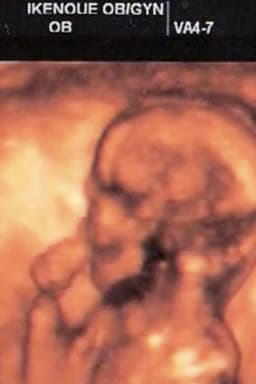

I went to the company to get up in the morning. And I saw a video taken by a mobile phone. It's a festival to raise the large kite that Hamamatsu festival of Shizuoka. They raise the kite when the first child is born. I was printing the video to OHP. And I cut it to 35mm film. I then projected it. My wife and I went to raise the kite to the park. I attached a camera to thekite. The ground looked like my wife's belly. My wife gave birth to a child. We named her "Nemu". She was born in 2005. Nemu became one year old. She became able to walk. I wanted to celebrate with everyone.